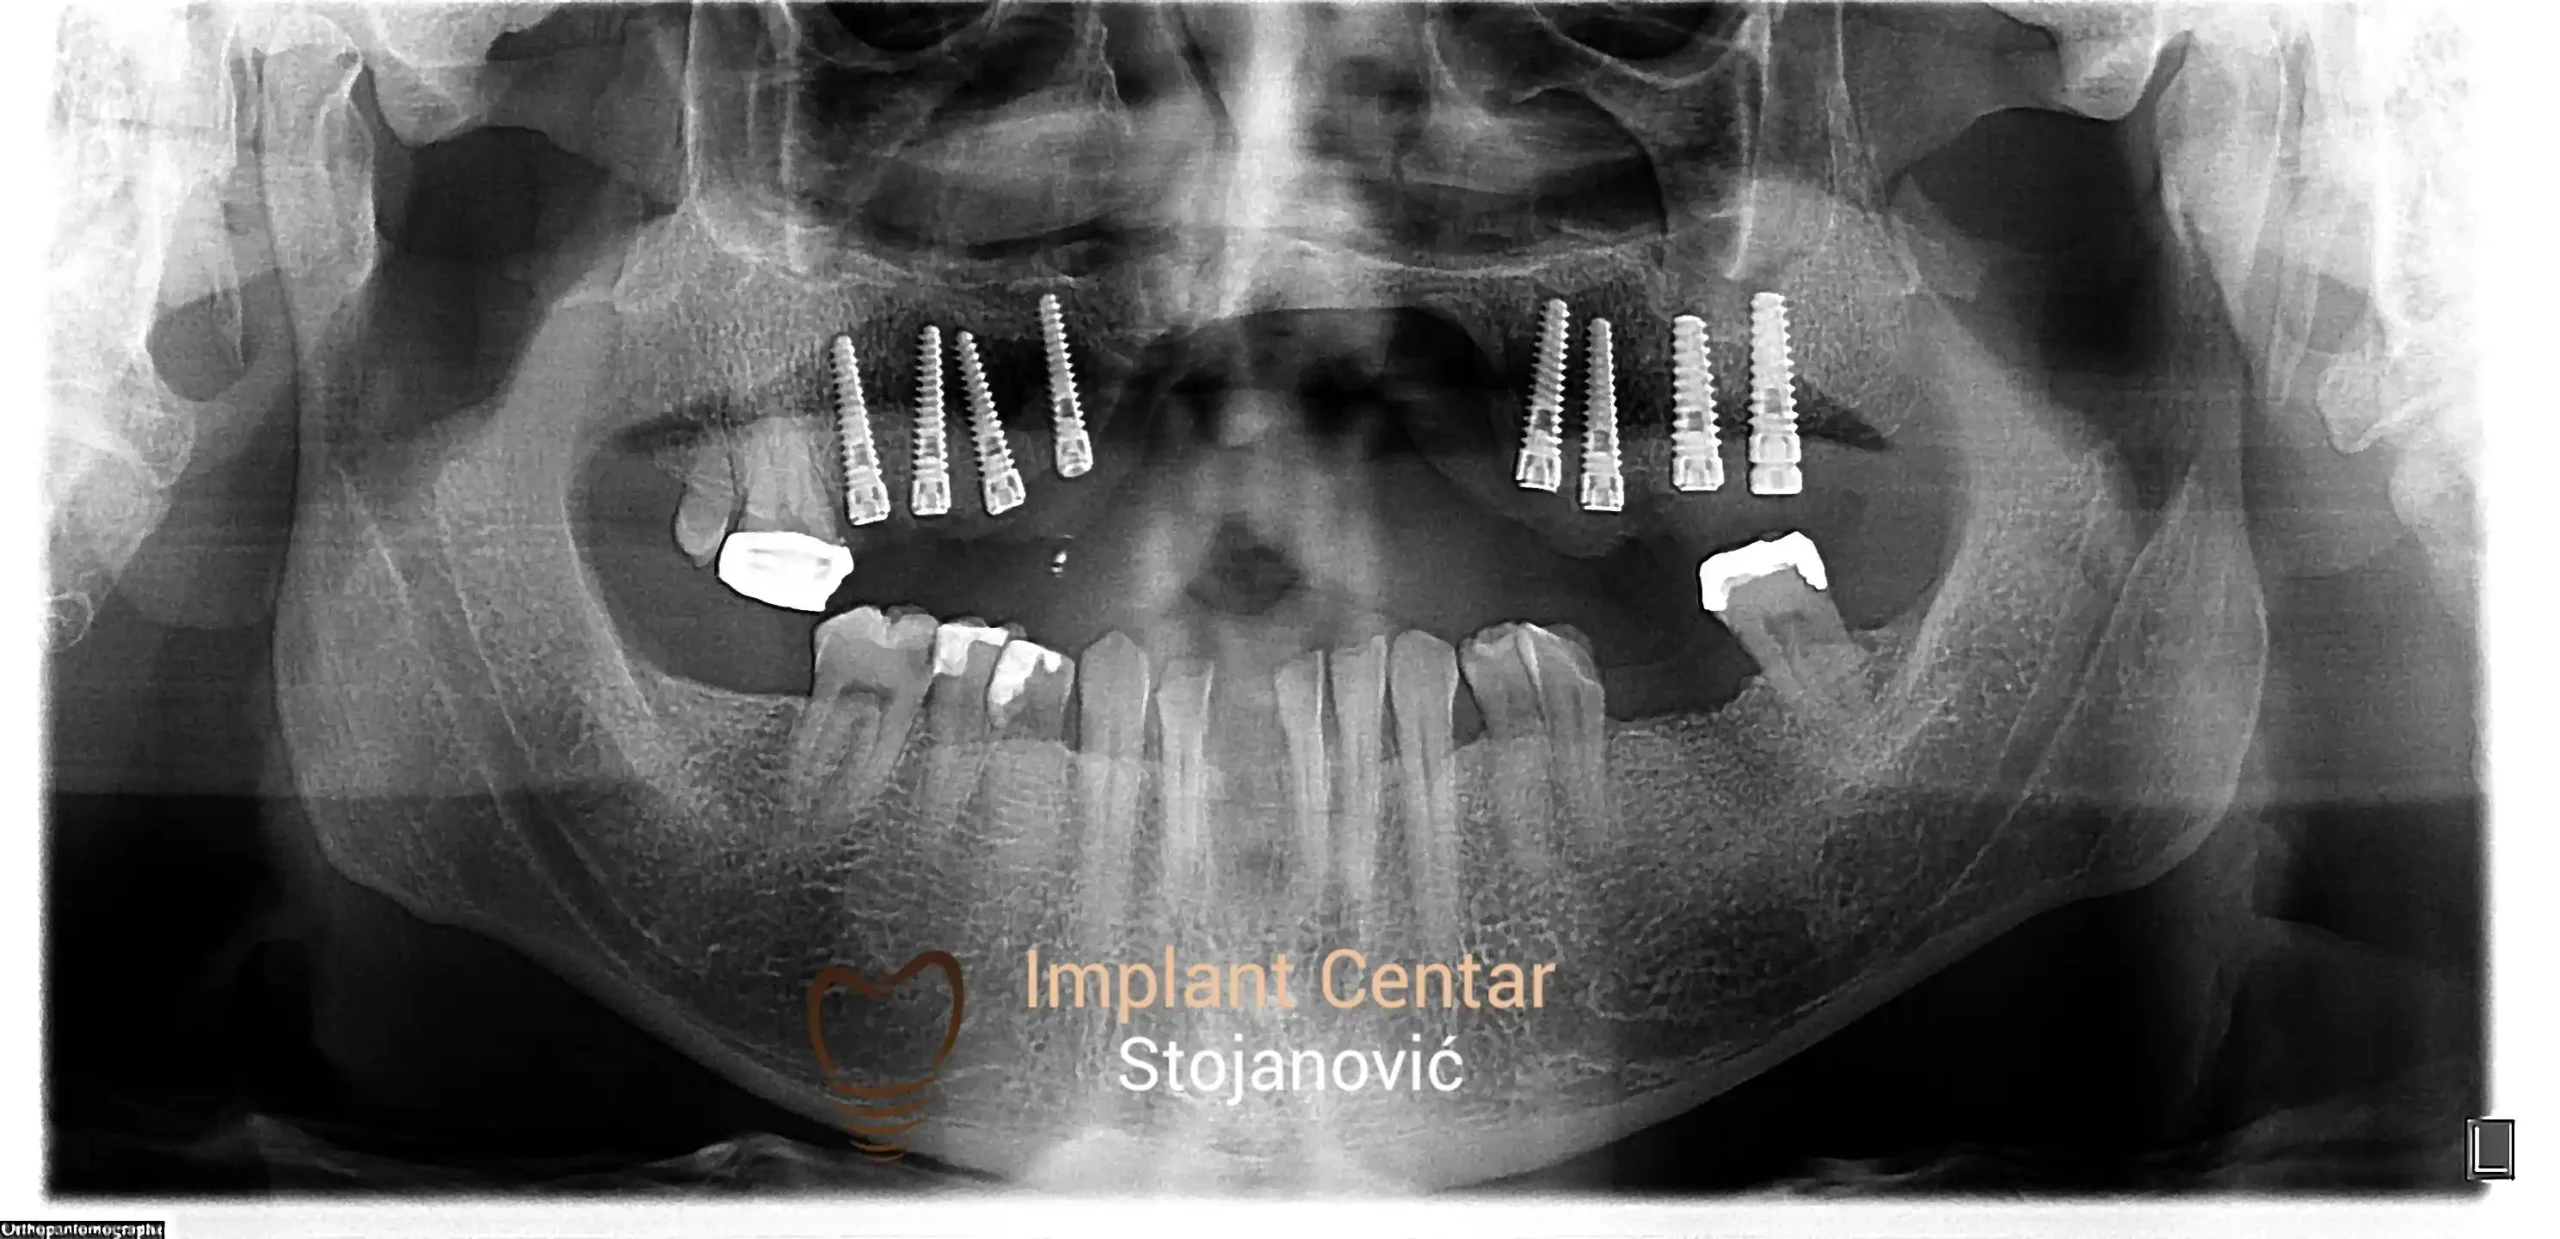

Na slici 1. i slici 2. prikazan je izgled pacijenta pre početka terapije – klinički i rendgenološki.

Nakon vađenja zuba, ugrađeni su implantati. Na slici 3 prikazan je ortopan snimak sa ugrđenim implantatima. Tokom perioda osteointegracije, pacijent je bio zbrinut fiksnim privremenim krunicama na implantatima, koje su izrađene samo dva dana nakon hirurške intervencije.